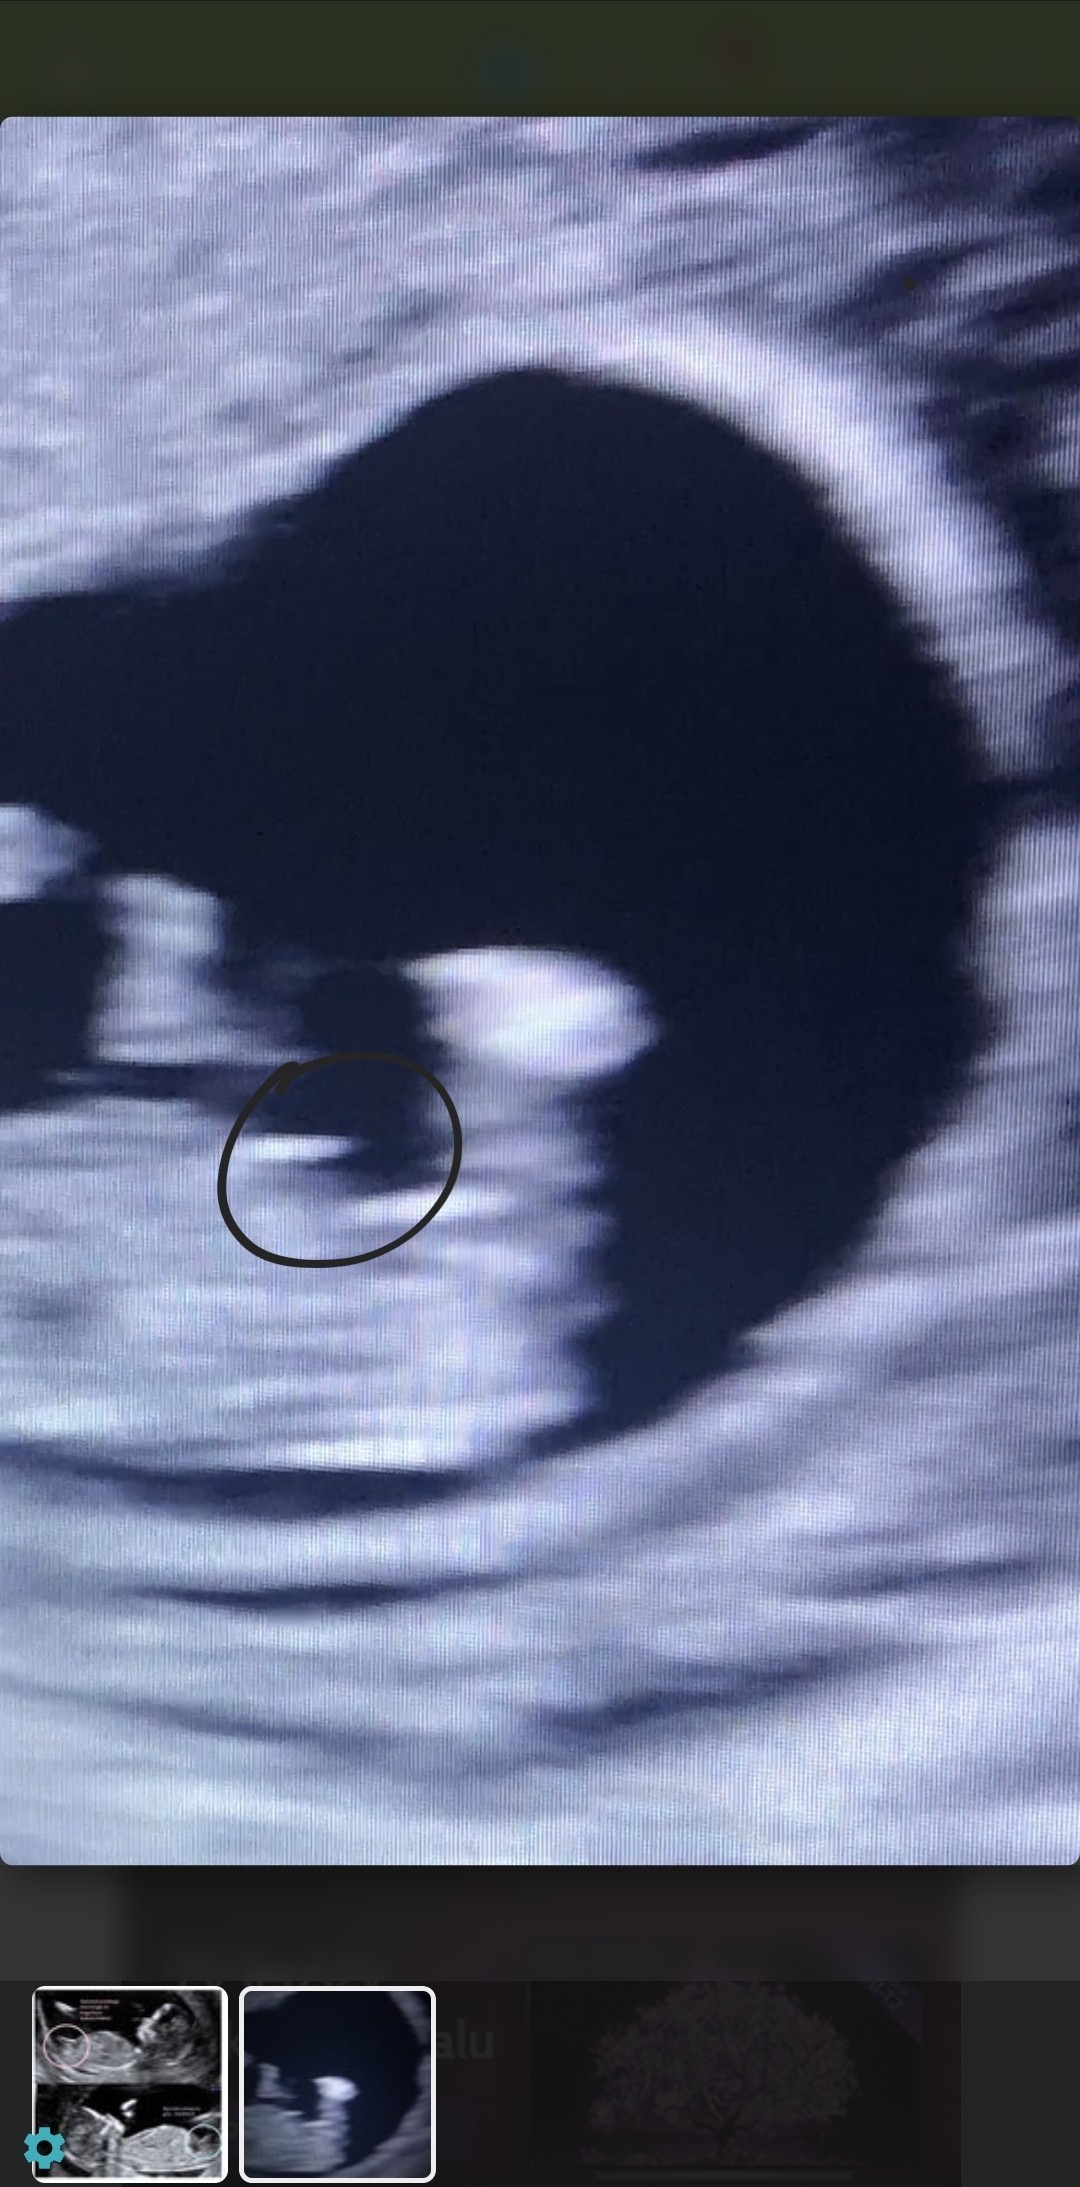

Wrzucam screen shot z mojego filmiku, na nim widać nóżki. Widzicie ten wyrostek na fotce? W artykule u mamyginekolog jest napisane, że jak wyrostek jest równoległy do kręgosłupa to to jest dziewczynka. Czy to możliwe, że u mnie coś widać, czy to jakiś przebłysk?

Usg robione było przez brzuch, więc na pewno nie jest idealne. Wrzucam też screen zdjęcia z artykułu.